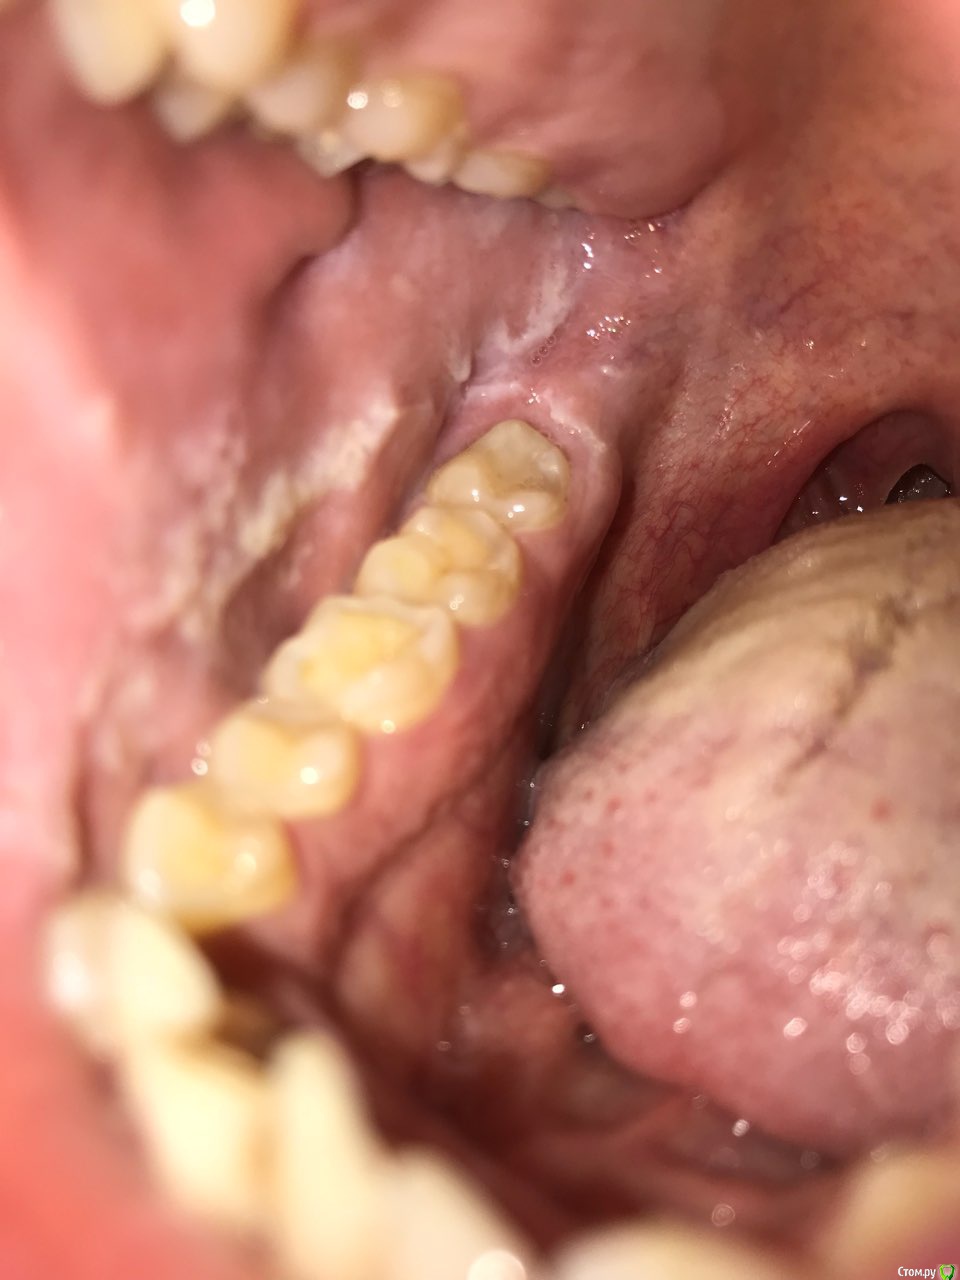

Антон Сафин Опубликовано 1 апреля, 2018 Поделиться Опубликовано 1 апреля, 2018 Последние несколько месяцев стал замечать что на стенках щек что-то стало образовываться в виде белого налета. Заглянул с фонариком увидел белые полоски + еще язык в белом налете часто, эти белые полоски на щеках не болят, не мешают, но бывает могу их кусать зубами отрывая и выплевывая как инородное тело. Что это за белые образования, опасно ли это? Как это лечить? Где-то в интернете наткнулся что это называется - Лейкоплакия, так ли это? Ссылка на комментарий

Борис80 Опубликовано 1 апреля, 2018 Поделиться Опубликовано 1 апреля, 2018 (изменено) поправьте гигиену полости рта для начала,в этих местах ( в области линии смыкания зубов) очень часто встречаются участки с подобным эпителием, с заболеваниями ЛОР органов часто сталкиваетесь? Если заметных улучшений не отметите, обратитесь очно к стоматологу Изменено 1 апреля, 2018 пользователем Борис80 Ссылка на комментарий

Антон Сафин Опубликовано 3 апреля, 2018 Автор Поделиться Опубликовано 3 апреля, 2018 если беленькое попробовать аккуратно счистить,что будет(на маленьком участке)Сложно сказать, но скорее не счищается, такое ощущение что это старые части слизистой такое может быть? Ссылка на комментарий

Антон Сафин Опубликовано 5 апреля, 2018 Автор Поделиться Опубликовано 5 апреля, 2018 стоматологу-терапевту.желательно специализаия-слизистыеСходил к терапевту и хирургу, терапевт сказал что этот белый налет что-то странное и отправил к хирургу, а он в свою очередь сказал что это не страшно, нужно удалять "восьмерки" и править прикус, мол из-за этого я прикусываю щеки, странно это, учитывая что про "проблемы" с зубами я знал давно и налета не было. К кому еще идти? п.с. зубы буду делать в ближайшее время. Ссылка на комментарий